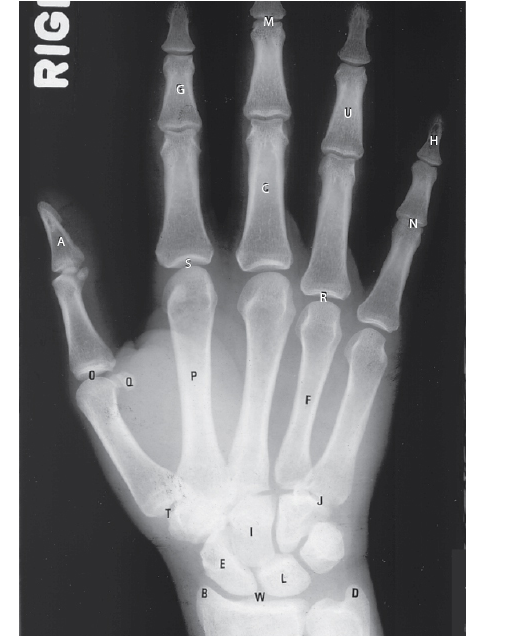

What type of joint is T?

The radiograph is a PA projection of the hand and wrist; an oblique projection of the thumb is obtained. The letter T is pointing out the first carpometacarpal joint, formed by the base of the first metacarpal and the trapezium. This is classified as a saddle type diarthrotic joint. Diarthrotic joints are freely movable joints and the most plentiful type of joint in the human body. Amphiarthrotic joints are partially movable; synarthrotic joints are immovable.